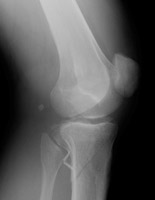

- Click on the image for a larger versionBOblique radiograph of the knee. The fracture of the tibia is visualized.